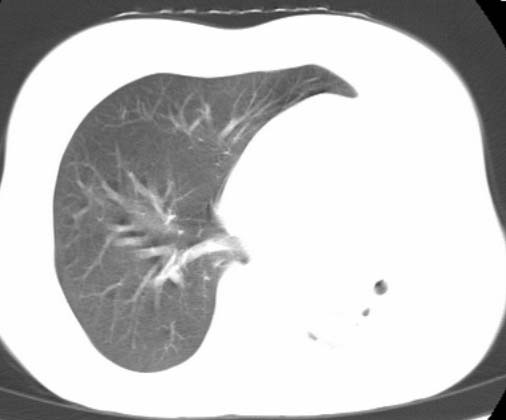

标题: CT25648:求教:是肺发育不全还是结核?

女  20岁。一月前咳血,诊“肺结核”抗痨治疗一月后,咳血停止,现复查。病人精神好。前后ct片对比未见明显变化。既往体检“正常”

1)考虑左肺结核并肺不张、支气管扩张。2)纵隔疝。

考虑左肺结核,左肺毁损,纵膈左偏,既往体检正常不可靠,tb一个月也不会这个样子的,有钙化,应该病程较长,冰冻三尺非一日之寒!

左肺发育不全。

考虑左肺结核,左肺毁损,纵膈左偏,既往体检正常不可靠,tb一个月也不会这个样子的,有钙化,应该病程较长,冰冻三尺非一日之寒

结核,左肺毁损。